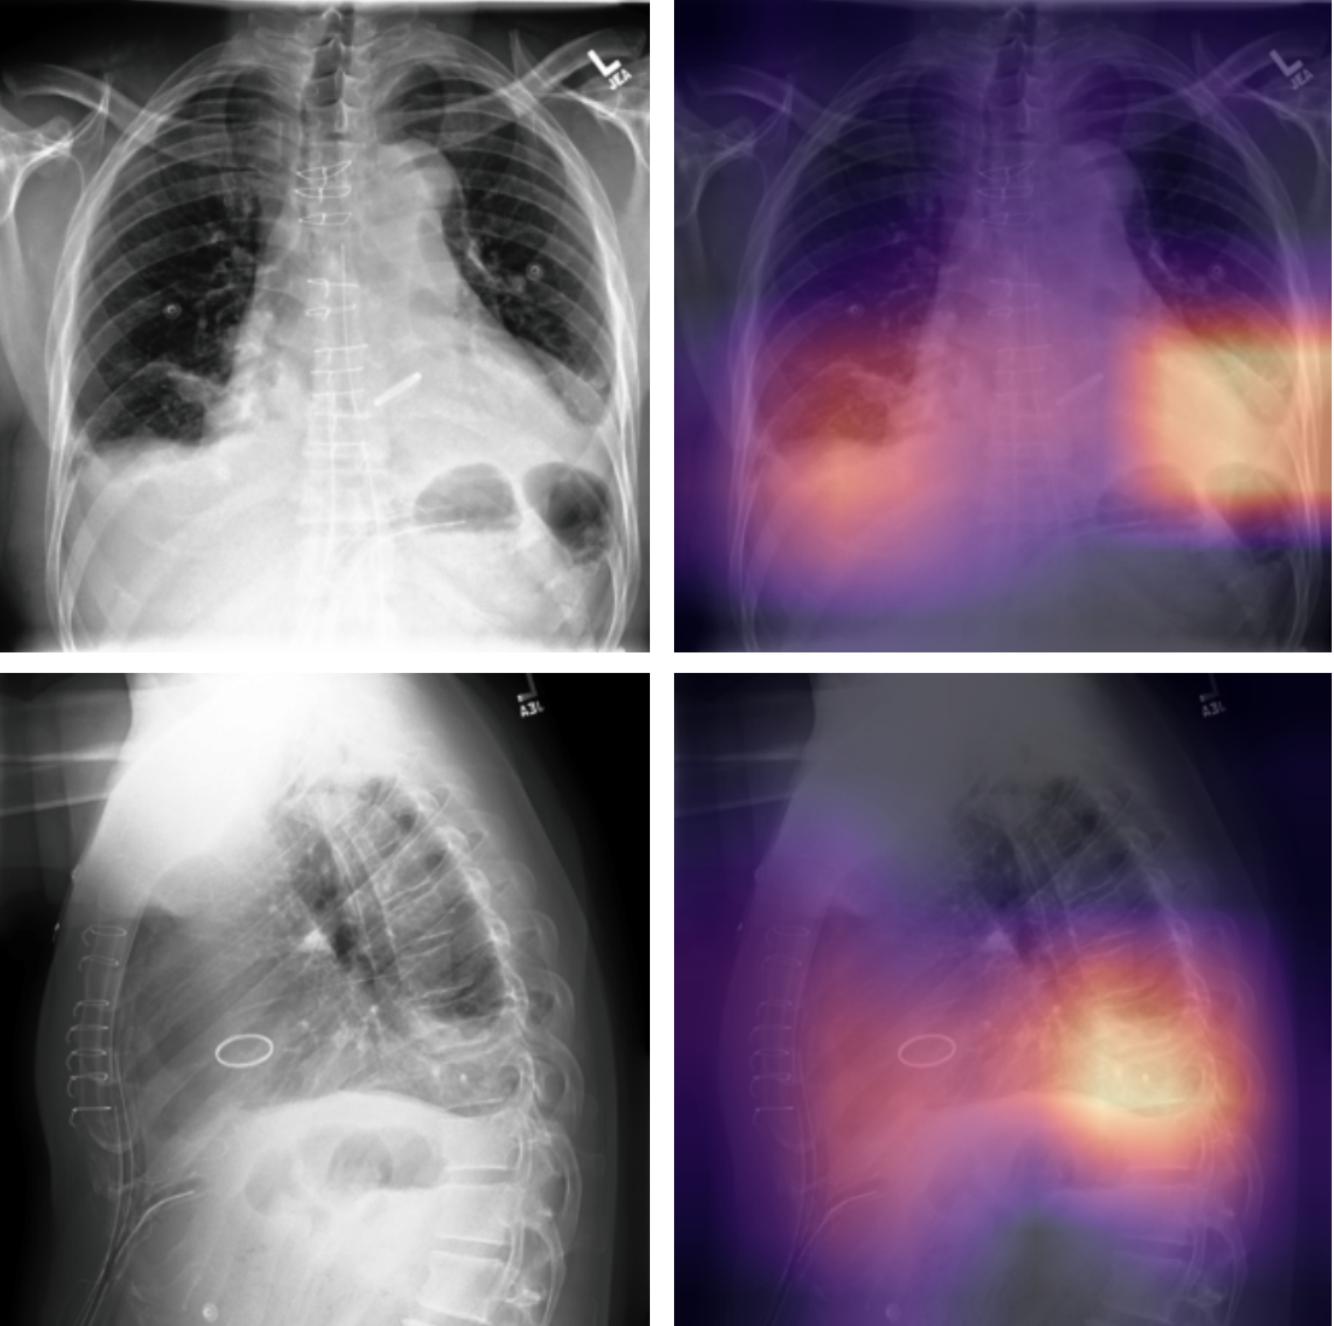

CheXpert Classification with EfficientNet B3 🫁⚕️

This Package contains EfficientNet B3 model which has been trained over CheXpert Small version for 30 epochs and can be used to classify chest X-ray images for 14 classes including:

chexpert_classifier(pathInputImage = '/content/download (3).jpeg',pathOutputImage = 'heatmap_view1_frontal.png',pathModel = '/content/m-epoch0-12072022-085549.pth.tar')